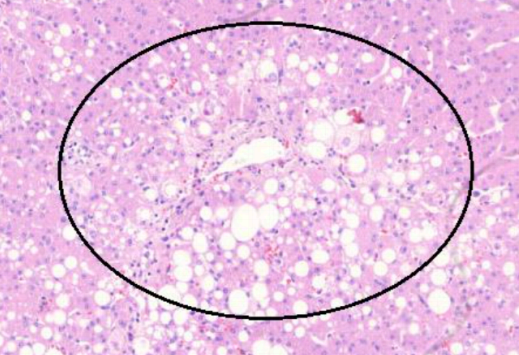

2. Esteato-hepatite (A502)

1. Gordura centro-lobular

1. Maior parte da gordura próxima ao espaço porta

2. Balonização

1. Acúmulo de gordura e água nos hepatócitos

2. Não há predomínio de fibrose